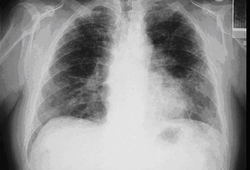

Kaposi sarcoma may cause persistent pulmonary infiltrate.[Figure caption and citation for the preceding image starts]: Posterior-anterior chest x-ray in Pneumocystis jiroveci pneumonia showing severe, bilateral pulmonary interstitial infiltrates with pneumatocelesFrom the collection of Matthew Gingo, UPMC [Citation ends].